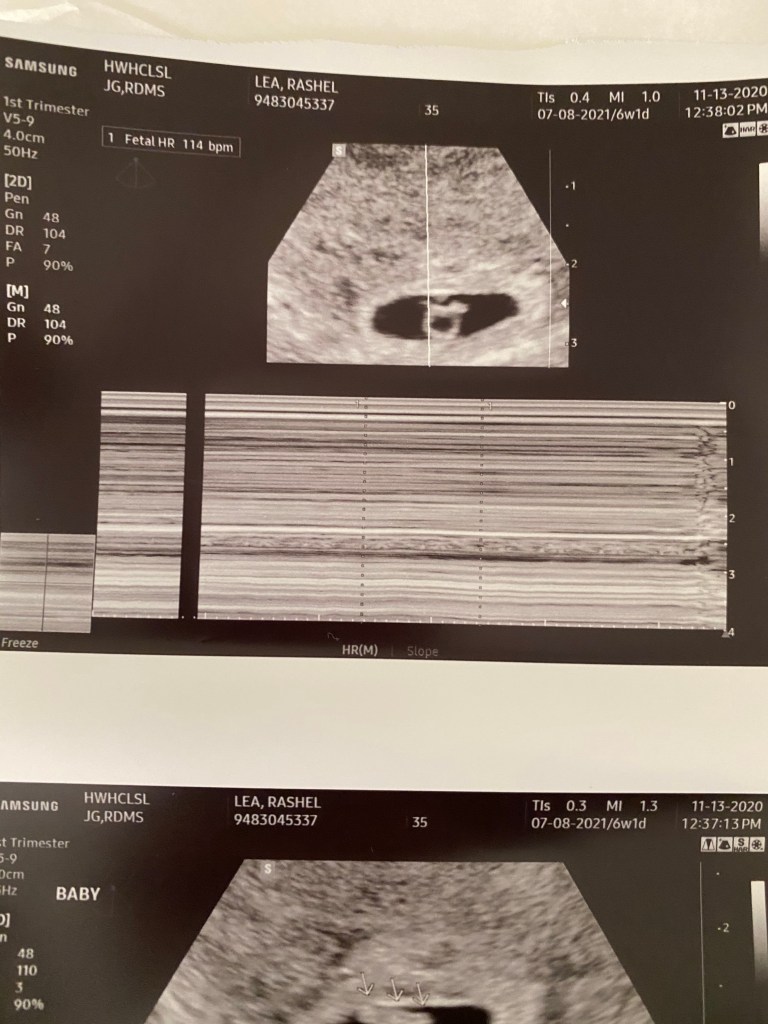

At first I was worried I could see the blob of the baby but I couldn’t see the flickering of the heartbeat. She assured me it was there and she could see it. She zoomed in and then I could too!! 😍 I immediately felt so so much better and calm. Then I was on the hunt making sure I only saw the one little guy. Good news for me it looks like it’s one strong little guy growing in there. I’m so relieved and happy for all of us.

The ultrasound technician said baby looks perfect and is measuring at 6 weeks and 4 days so a little bigger then we’re we are. I should be 6 weeks one day since we know the exact moment he went in 😂. His heart rate is a solid 114 so that’s great too. So much joy and happiness today.